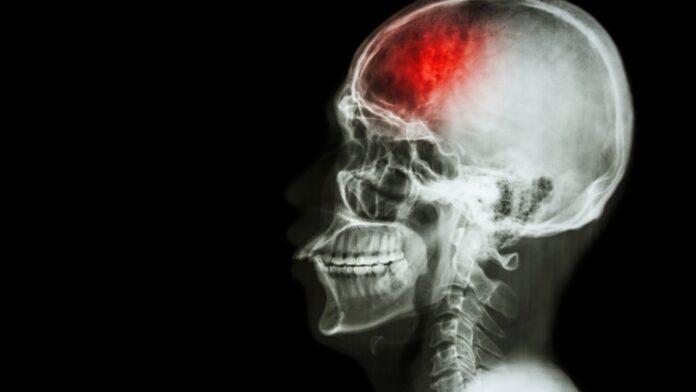

Globalmente, o número de casos de AVC aumentou 70% entre 1990 e 2021, segundo a pesquisa feita pela Revista de neurologia, Lancet. No Brasil, quase 35 mil pessoas perderam a vida em razão do AVC somente no primeiro semestre de 2024, de acordo com o Portal de Transparência do Registro Civil (ARPEN Brasil). Esses números nos mostram a importância de estudar essa condição neurológica com efetividade, já que ela é uma emergência médica que requer diagnóstico e tratamento rápidos para minimizar danos cerebrais e melhorar o prognóstico.

O diagnóstico do AVC hemorrágico é geralmente feito por meio de uma tomografia computadorizada (TC) de crânio, que é o exame de escolha em situações de emergência. Na TC, a hemorragia aparece como uma área hiperdensa (branca). Outros sinais que podem ser observados incluem o “spot sign”, que indica extravasamento de contraste dentro do hematoma, sugerindo um possível aumento da hemorragia.